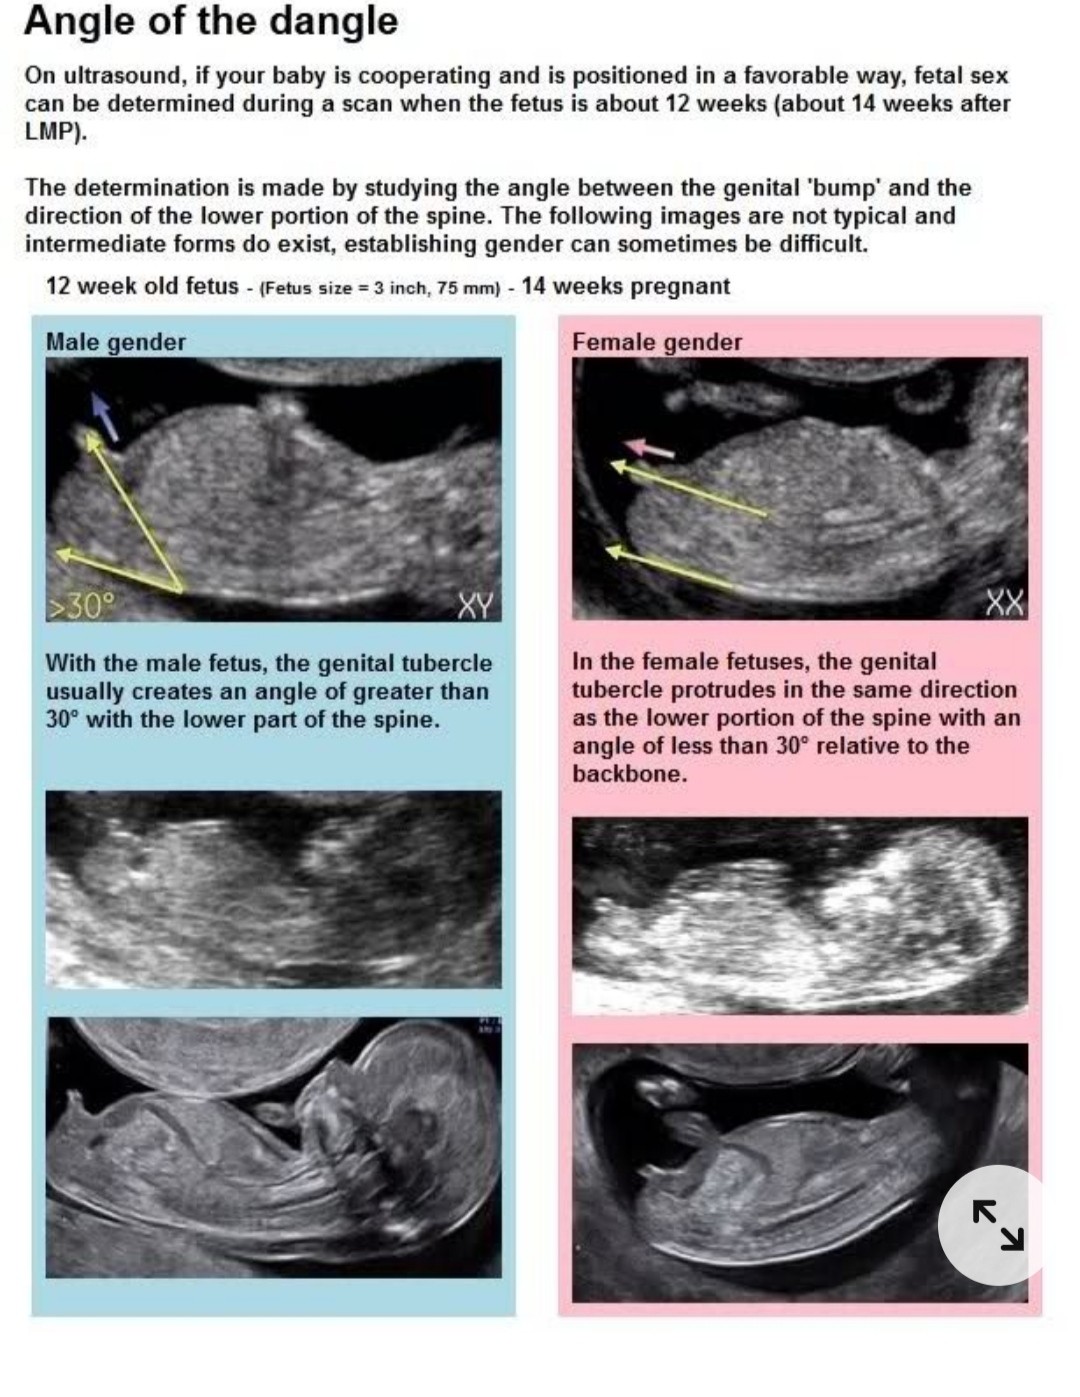

Na podstawie wyrostka i jego kąta...